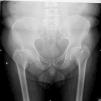

Caso clínicoVarón de 59 años con antecedente personal de diabetes mellitus tipo 2 en tratamiento con antidiabéticos orales, que acude a consulta de Reumatología por dolor inguinal bilateral y dorsolumbalgia de intensidad dolorosa progresiva, ambos de ritmo mecánico, que el paciente califica de muy intenso y que desencadenan dificultad progresiva para la deambulación; y por episodios de disnea de moderados esfuerzos, cuyo origen, estudiado por Neumología, era debido a dificultades en la expansión torácica. El cuadro doloroso no había presentado una respuesta satisfactoria a antiinflamatorios no esteroideos ni a opiáceos menores. En la exploración física se observa talla de 146cm, marcada cifosis dorsal, obesidad troncular, limitación importante para la flexoextensión y las rotaciones de ambas articulaciones coxofemorales, y braquidactilia en ambas manos. Hemograma y bioquímica sanguínea con valores normales. El estudio radiológico convencional de columna dorsolumbar, anteroposterior de pelvis y posteroanterior de manos se muestran en las figuras 1 a 4.

El paciente descrito presenta datos que sugieren una displasia espondiloepifisiaria tarda. Esta entidad tiene una herencia recesiva ligada al cromosoma X1, estando por lo tanto afectados sólo los varones. Se han descrito mutaciones en el gen SELD en el cromosoma Xp22.12-p 23.311. El diagnóstico se realiza entre los 5 y los 10 años de edad, cursando con enanismo de tronco corto; esto es, retraso en el crecimiento de la columna vertebral con una talla media final de 145cm y desproporción entre la longitud de las extremidades y el tronco2,3. La articulación coxofemoral está siempre afectada en coxa vara con aplanamiento leve de las epífisis, que conducen a cambios artrósicos precoces, y que pueden, en estadios más avanzados, incapacitar al paciente2–4. A nivel axial se describen cambios displásicos vertebrales con platiespondilia, que provocan cifosis progresiva4–6 con aumento del diámetro anteroposterior del tórax, y que en último término puede provocar episodios de disnea. No aparece retraso mental, se han descrito formas familiares con asociación a condrocalcinosis7,8 y existe una forma de displasia espondiloepifisiaria tarda asociada a artropatía degenerativa precoz, que puede simular artritis reumatoide juvenil9.